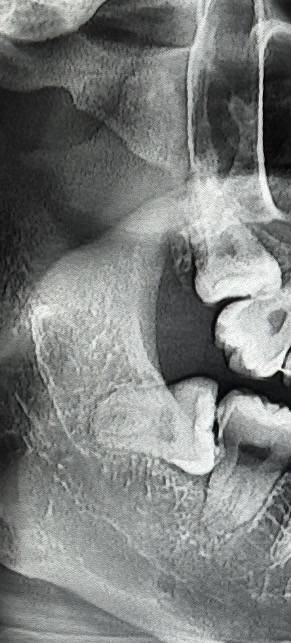

사랑니 잘알있어? 난이도 높은거야?

매복 저정도는 무난

개쉬움

잘하는 곳 가면 하나에 1-2분 컷 함 마취시간 빼고

동네치과에서 빠꾸 먹고 대학병원가라는데 대학병원까지 가야하나해서 ..

동네치과는 당연히 에바고 ㅣㅋㅋㅋㅋ 걍 근처 구강악안면외과 가면 돼 대병도 에바임

신경이랑 엄청 가까운 편도 아니어스

나랑똑같네 그냥뺐어! 아프지도 않았옹